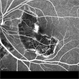

- macula serpiginous choroidopathy, Optos, fundus autofluorescence (FAF), macula lesion, ultra-wide field imaging, fundus photograph

- Optos ultra wide field auto fluorescent image of 20-year-old female presenting with serpiginous choroidal atrophy. Patient was unaware of vision loss OD, until accidentally covering OS and noticing the change. Acuity of 20/200 OD and 20/15 OS at time of imaging.